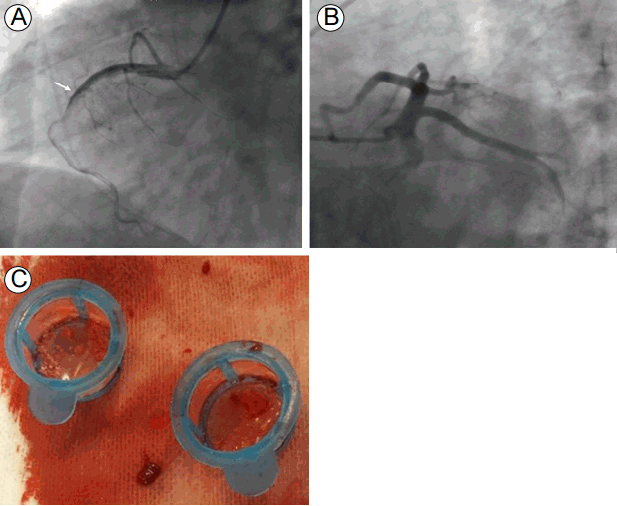

Figure 3.

(A) The emergency coronary angiography shows thrombotic occlusion in the proximal to middle right coronary artery (arrow), and (B) the normal left anterior descending and circumflex arteries. (C) The thrombi aspirated from the right coronary artery.